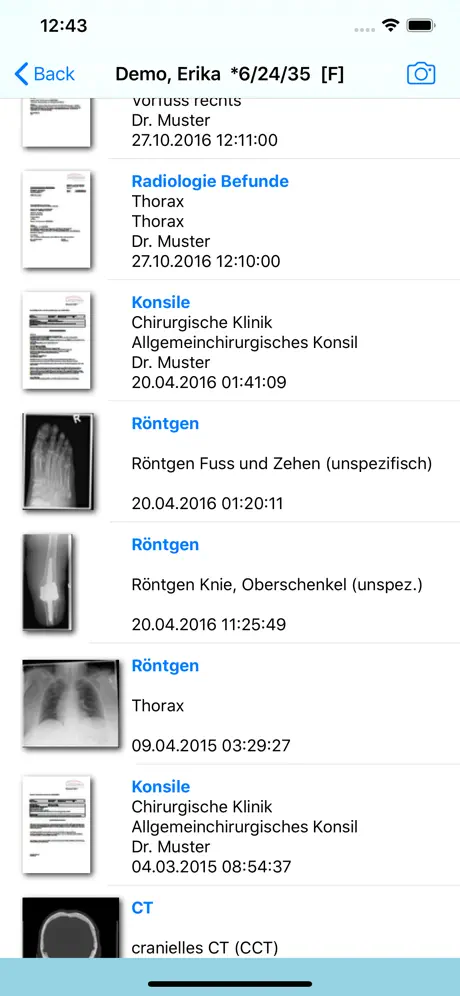

- Thumbnailvorschau

- Filterfunktionen auf Dokumentenarten

- Filterfunktionen auf Fälle

- Anzeige von Dokumenten

- Anzeige von Fotos

- Thumbnailvorschau

- Filterfunktionen auf Dokumentenarten

- Filterfunktionen auf Fälle

- Anzeige von DICOM Objekten

- Anzeige von Dokumenten

- Anzeige von Fotos